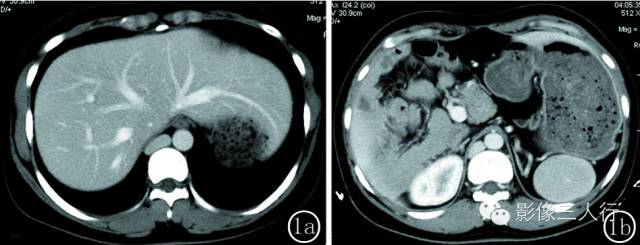

图 2 女性 , 52 岁 。 图 2a 水平肝 ,胃 、脾反位 ,均位于右季肋区 ,脾呈多个大小不等的结节 ,肝段下腔静脉缺如 ,奇静脉及半奇静脉异常增粗 。 图 2b冠脉位重建图像 :右侧季肋区可见 6 个大小不等的小脾脏 。 图 2c 胰腺反位 ,胰腺体尾部发育短小 ,胰腺周围可见渗出 ,双侧肾静脉回流入奇静脉